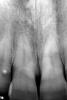

Елка Опубликовано 10 октября, 2009 Поделиться Опубликовано 10 октября, 2009 Добрый день!Помогите пожалуйста, что с моим зубом. На снимке левый передний. Врач после чистки канала с казала, что сломан корень зуба и его нужно удалять. Зуб болит, имеется свишь между передними зубами, но опухоль уже спала. Зуб немного подвижный. Естественно мне очень хочется сохранить зуб. Я сомневаюсь по поводу перелома, т.к. на первом снимке то, что мне показывают как перелом видно на правом зубе. А на втором на левом. В случае, если это дествительно перелом, есть ли шанс спасти зуб? Ссылка на комментарий

zybnaya feya Опубликовано 10 октября, 2009 Поделиться Опубликовано 10 октября, 2009 какая разница во времени между снимками?и почему перелом приключился? травмы были? по снимку - похоже на перелом.если это поперечный перелом корня - есть шанс убрать зуб и поставить имплант. пока есть кость. и красиво с десной получится.мож, снимок еще сделать в канале с контрастом? или КТ?+1 на втором снимке видна линия перелома. И изменения уже в косной ткани. Зуб на удаление Ссылка на комментарий

zybnaya feya Опубликовано 10 октября, 2009 Поделиться Опубликовано 10 октября, 2009 Разница во времени неделя. Первый снимок до вскрытия канала. травма была пол года назад -удар восковым мелком. Меня смущает, что на первом снимке ничего не видно....Ну конечно на первом снимке "ничего не видно" вы же его перевернули слева направо . Посмотрите что 2-ка(на ней беленькая точечка,как маркер оказался на первом снимке у вас с левой стороны,а на втором с правой). Там линия перелома видна на обоих снимках(только на первом снимке смотреть надо на тот зуб который правее) http://i011.radikal.ru/0910/7b/6e2edc533be3.jpghttp://s51.radikal.ru/i132/0910/4e/6f2cd2a7d85a.jpg Ссылка на комментарий

zybnaya feya Опубликовано 10 октября, 2009 Поделиться Опубликовано 10 октября, 2009 (изменено) фей у автора не догон что ты там хотела показать своими "кружочками"она может в школе не училась-физики не знаетто такое стереоизомеры тоже не знаетвообще что изомерия и симметрия не знаетпро фокус с зеркальным изображением вообще молчуу неё может и зеркала дома нет.суть не в этомтут я как погляжу оба резца "переломанные" ну я еше не знаю как обьяснить по простому,про изомерию и симметрию я уж и не стала ничего говорить,если уже и наглядно обвела и не понятно,я не в силах помочь)))) Ну в одном из резцов перелом есть это точно,иначе резорбции не было бы в области линии перелома. (с номером зуба я уже сама затрудняюсь,ибо снимки перевернуты). Просто пациенту не хочеться видеть проблему ДО вмешательства доктора,а хочеться чтоб тут все сказали,что теперлом появился ПОСЛЕ лечения. А ЭТО НЕ ТАК Изменено 10 октября, 2009 пользователем zybnaya feya Ссылка на комментарий

Чиффа Опубликовано 10 октября, 2009 Поделиться Опубликовано 10 октября, 2009 Ёлка! снимки не должны быть идеально идентичны! их же с помощью человека делают: чуть смести трубку или датчик визиографа, и вуаля! и корни разной длины, и смотрят в разные стороны....по снимкам перелом на одном и том же зубе и на первом снимке и на втором. о его перспективах Вам уже написали. Ссылка на комментарий